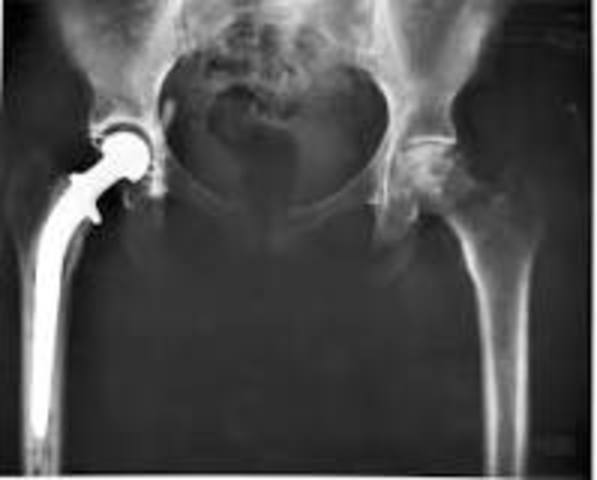

• Hip Replacement

Hip Replacement

Dr. Austin Moore performed the first metallic hip replacement leading to the advancement of safely and effectively replacing hips.